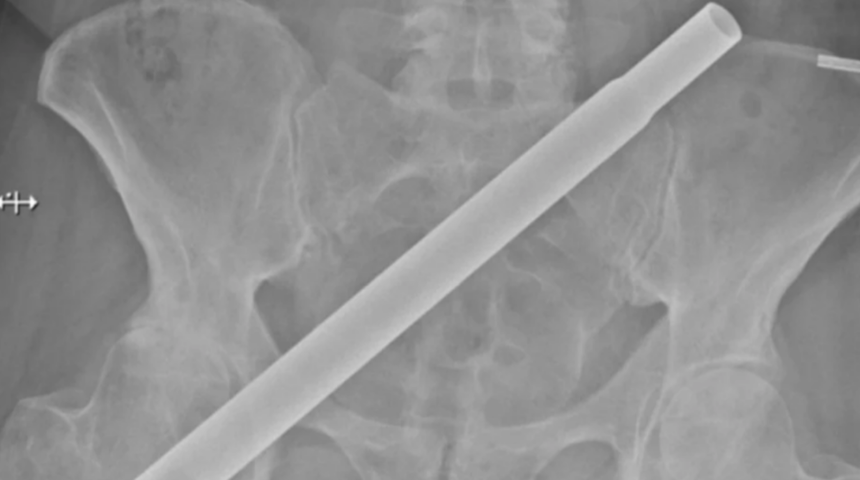

Dünya üzerinde ilginç bir sürü travmatik yaralanma vakaları bulunuyor. Kuzey İrlanda, Newry'den 54 yaşındaki bir kadın yılbaşı ağacının metal direğinin üzerine düşmesiyle birlikte korku dolu anlar yaşadı. Vaka, klinik vaka raporları tıp dergisinde doktorlar tarafından açıklandı. Dimitrios Angelou ve meslektaşları, travmatik yaralanmalar söz konusu olduğunda hastanelerde hızlı hareket etmenin önemini belirtti. Dediler ki: "Hastamız, bir merdivenden yapay bir Noel ağacının metalik tabanına düşmüş ve ağacın gövdesi onun sağ kalçasından geçerek pelvisine saplanmış.

Gazete, itfaiyenin kadının CT tarayıcısına sığabilmesi için metal direği kesmesinin bir buçuk saat sürdüğünü söyledi. “Etkileyici yaralanma mekanizmasına rağmen, yaşamı tehdit eden bir kanama olmadı…” Yapılan açıklamalar direğin nasıl çıkarıldığı veya hastanın iyileşmesinin ne kadar sürdüğü hakkında ayrıntılar içermiyordu. Kadın şunları yazdı: “Ambulanstan hastaneye kadar mükemmel bir bakım ve ilgi gördüğümü eklemek istiyorum. Hastanedeki tüm personeller son derece kibar ve destekleyiciydi. Hayatımı onlara borçluyum.”